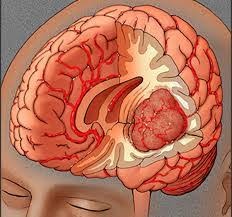

Οι όγκοι εγκεφάλου είναι καλοήθεις ή κακοήθεις. Οι συχνότεροι κακοήθεις όγκοι στους ενήλικες είναι οι μεταστάσεις από κακοήθεις όγκους άλλων οργάνων. Οι συχνότεροι πρωτοπαθείς κακοήθεις όγκοι είναι τα γλοιώματα και...